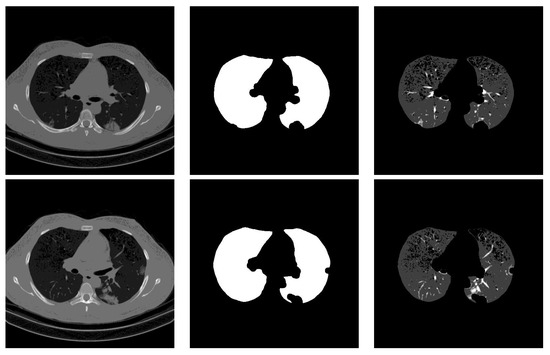

For lung segmentation, we used marker-based watershed segmentation [28], which is based on identifying two markers. The internal marker identifies the lung tissue, and the external marker identifies the outside of the region of interest. The internal marker is obtained by thresholding the image and removing all regions and leaving just the biggest one. The external marker is created by morphological dilation of the internal marker with two different iterations and subtracting the results. A watershed marker is created superimposing the two markers with different gray-scale values. To find the precise border of the lung, the marker-based watershed algorithm is applied on the black strip of the watershed marker and the Sobel gradient image of the original scan. In order not to miss lobes located next to the border regions, a black top-hat operation is performed to re-include those areas and areas surrounding the lung hila. Finally, the segmented lungs mask is obtained by holes closing. Figure 1 shows some examples of the lung segmentation for infected slices with COVID-19 and Cap diseases.

Figure 1.

Lung segmentation examples: the first column shows the input CT scan slice, the second column shows the lungs mask result, and the last column shows the lung segmentation results. The corresponding classes for rows 1 to 3 are COVID-19, COVID-19, and Cap, respectively.